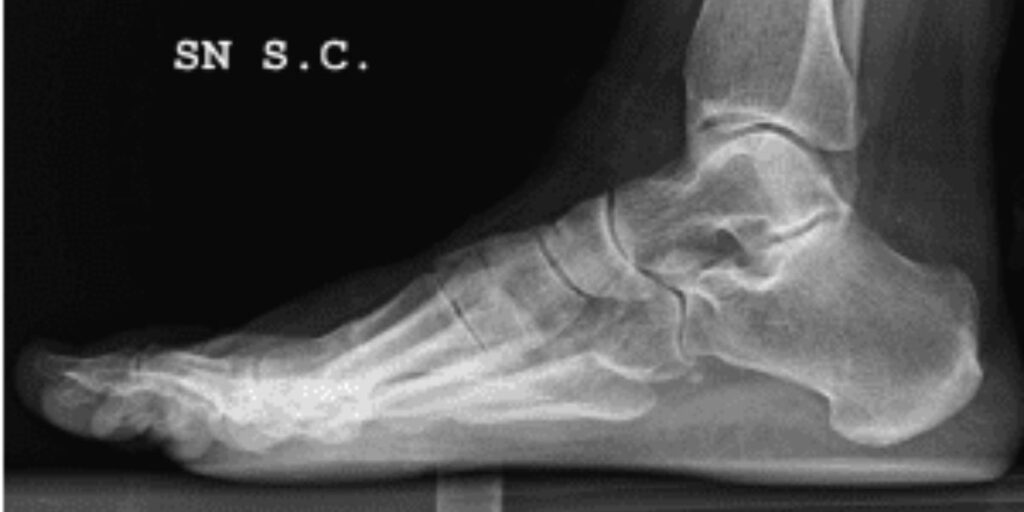

L’RX Tibio-Tarsica è una radiografia mirata all’esame delle ossa e delle articolazioni del piede e della caviglia. Questo esame sfrutta i raggi X per catturare immagini ad alta risoluzione, che mostrano eventuali anomalie come fratture, distorsioni o patologie degenerative. Grazie alla sua precisione, l’RX Tibio-Tarsica rappresenta uno degli strumenti più utilizzati per identificare problemi muscoloscheletrici e alterazioni strutturali in questa zona del corpo.

Attraverso l’RX Tibio-Tarsica, è possibile ottenere immagini precise delle ossa e delle articolazioni della caviglia e del piede, evidenziando fratture, dislocazioni, tumori ossei e altre alterazioni strutturali. Questo esame consente ai medici di individuare con facilità la presenza di anomalie che potrebbero non essere rilevabili con altre metodiche diagnostiche.

• Deformità congenite come il piede piatto o cavo.